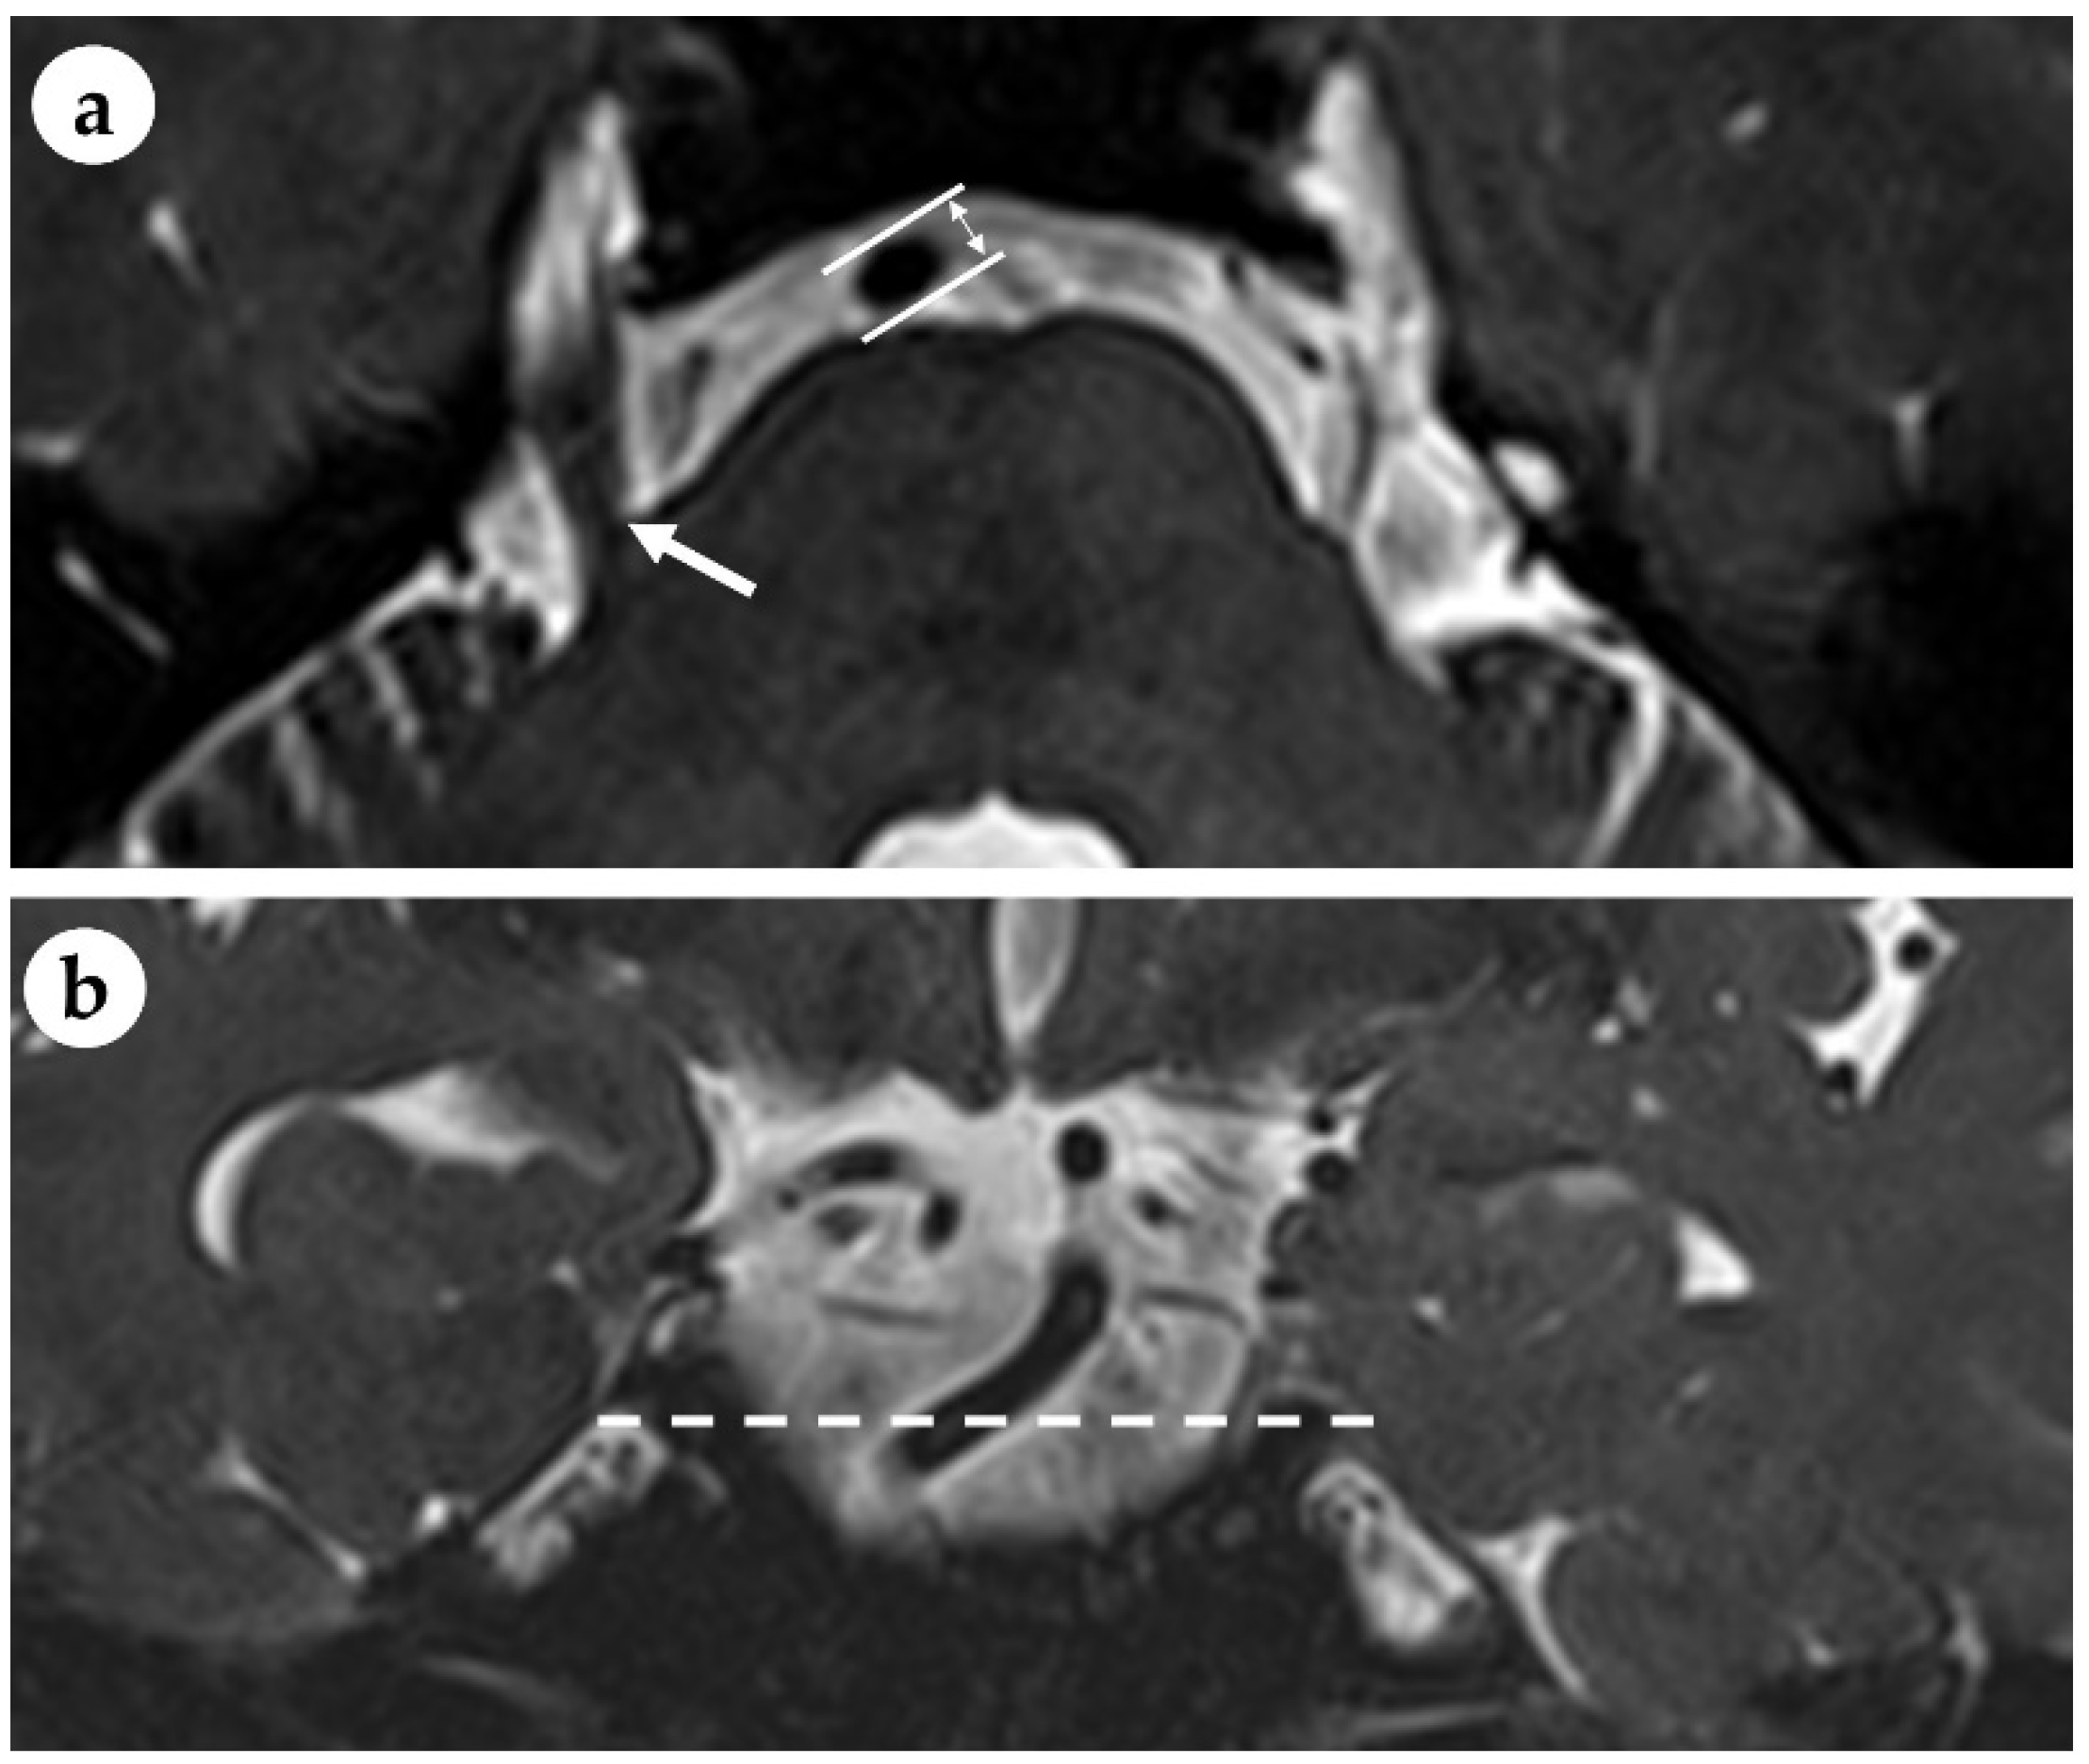

- Kim, C.; Sohn, J.-H.; Jang, M.U.; Hong, S.-K.; Lee, J.-S.; Kim, H.-J.; Choi, H.-C.; Lee, J.H. Ischemia as a potential etiologic factor in idiopathic unilateral sudden sensorineural hearing loss: Analysis of posterior circulation arteries. Hear. Res. 2016, 331, 144–151. [Google Scholar] [CrossRef]

- Huh, G.; Bae, Y.J.; Woo, H.J.; Park, J.H.; Koo, J.W.; Song, J.J. Vestibulocochlear Symptoms Caused by Vertebrobasilar Dolichoectasia. Clin. Exp. Otorhinolaryngol. 2020, 13, 123–132. [Google Scholar] [CrossRef]

- Gilbow, R.C.; Ruhl, D.S.; Hashisaki, G.T. Unilateral Sensorineural Hearing Loss Associated with Vertebrobasilar Dolichoectasia. Otol. Neurotol. 2018, 39, e56–e57. [Google Scholar] [CrossRef]

- Wang, Y.; Huang, J.; Qian, G.; Jiang, S.; Miao, C. Study on the Correlation between different Levels of Patients with Vertebrobasilar Dolichoectasia and Posterior Circulation Blood Perfusion. J. Stroke Cerebrovasc. Dis. 2022, 31, 106378. [Google Scholar] [CrossRef]